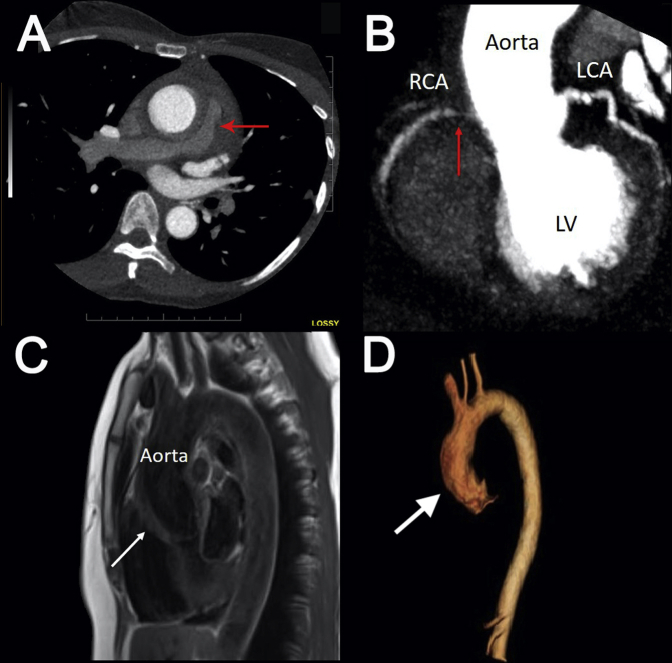

Contrast-enhanced cardiac CT was then arranged to definitively exclude an aortic dissection and intramural hematoma and to assess the coronary arteries. Cardiac CT demonstrated infiltrative soft tissue surrounding the aortic root and proximal ascending aorta, resulting in stenosis of the pulmonary trunk and right pulmonary artery (Figure 3A). There was infiltrative soft tissue surrounding the ostium of the right coronary artery, resulting in a long segment of 70% to 99% stenosis (Figure 3B, red arrow). There was infiltrative soft tissue around the left main coronary artery but no stenosis. There was no aortic dissection or intramural hematoma.

Figure 3.

Cardiac CT showing compression of the right pulmonary artery (A) proximal right coronary artery stenosis (red arrows) due to aortic root infiltration (B). (C) Cardiac MRI from the sagittal view demonstrating increased wall thickening and inflammation of the aortic root (white arrow), ascending aorta, and proximal aortic arch. (D) Cardiac MRI three-dimensional reconstruction showing thickening of the aortic root (white arrow), ascending aorta, and proximal aortic arch and sparing the other aortic segments. LCA, Left coronary artery; LV, left ventricle; RCA, right coronary artery.

In the absence of an acute aortic syndrome, cardiac MRI was ordered to characterize the infiltrative soft tissue surrounding the aorta. This showed diffuse wall thickening with late gadolinium enhancement (Figure 3C, white arrow) of the ascending aorta, which suggested diffuse inflammation. No such changes were seen in the descending thoracic aorta and abdominal aorta (Figure 3D, Video 9). On the basis of the cardiac MRI results, a diagnosis of aortitis was made.